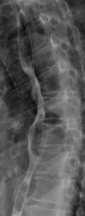

Treatment Planning Image for Carbon Ion Radiotherapy

Before Photon Radiotherapy Before Carbon Ion Radiotherapy After Carbon Ion Radiotherapy 1 Month After CarboRadiotherapy